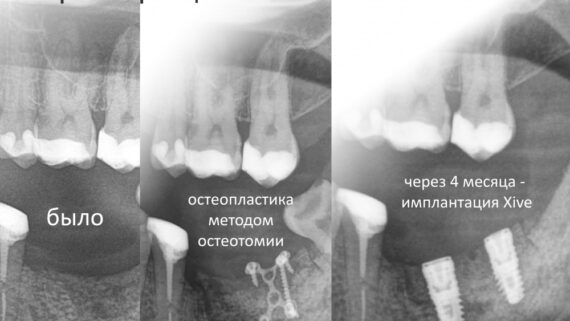

Через три месяца пациентка пришла ко мне на профилактический осмотр. Вот картинка:

Как видите, семерка делает успехи. Спасибо ортодонтам!